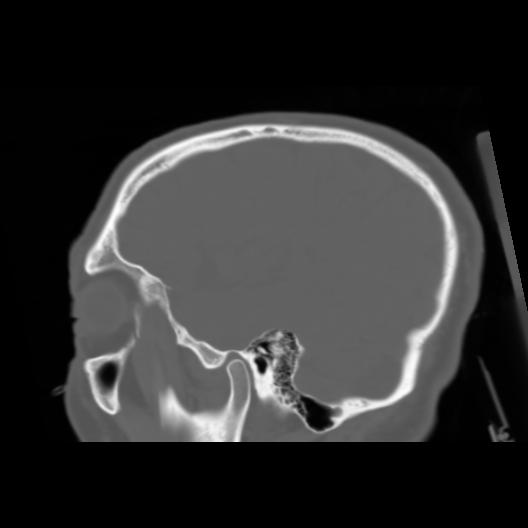

6 CEREBRO,,Sagittal,3.000,CEREBRO,Sagittal,